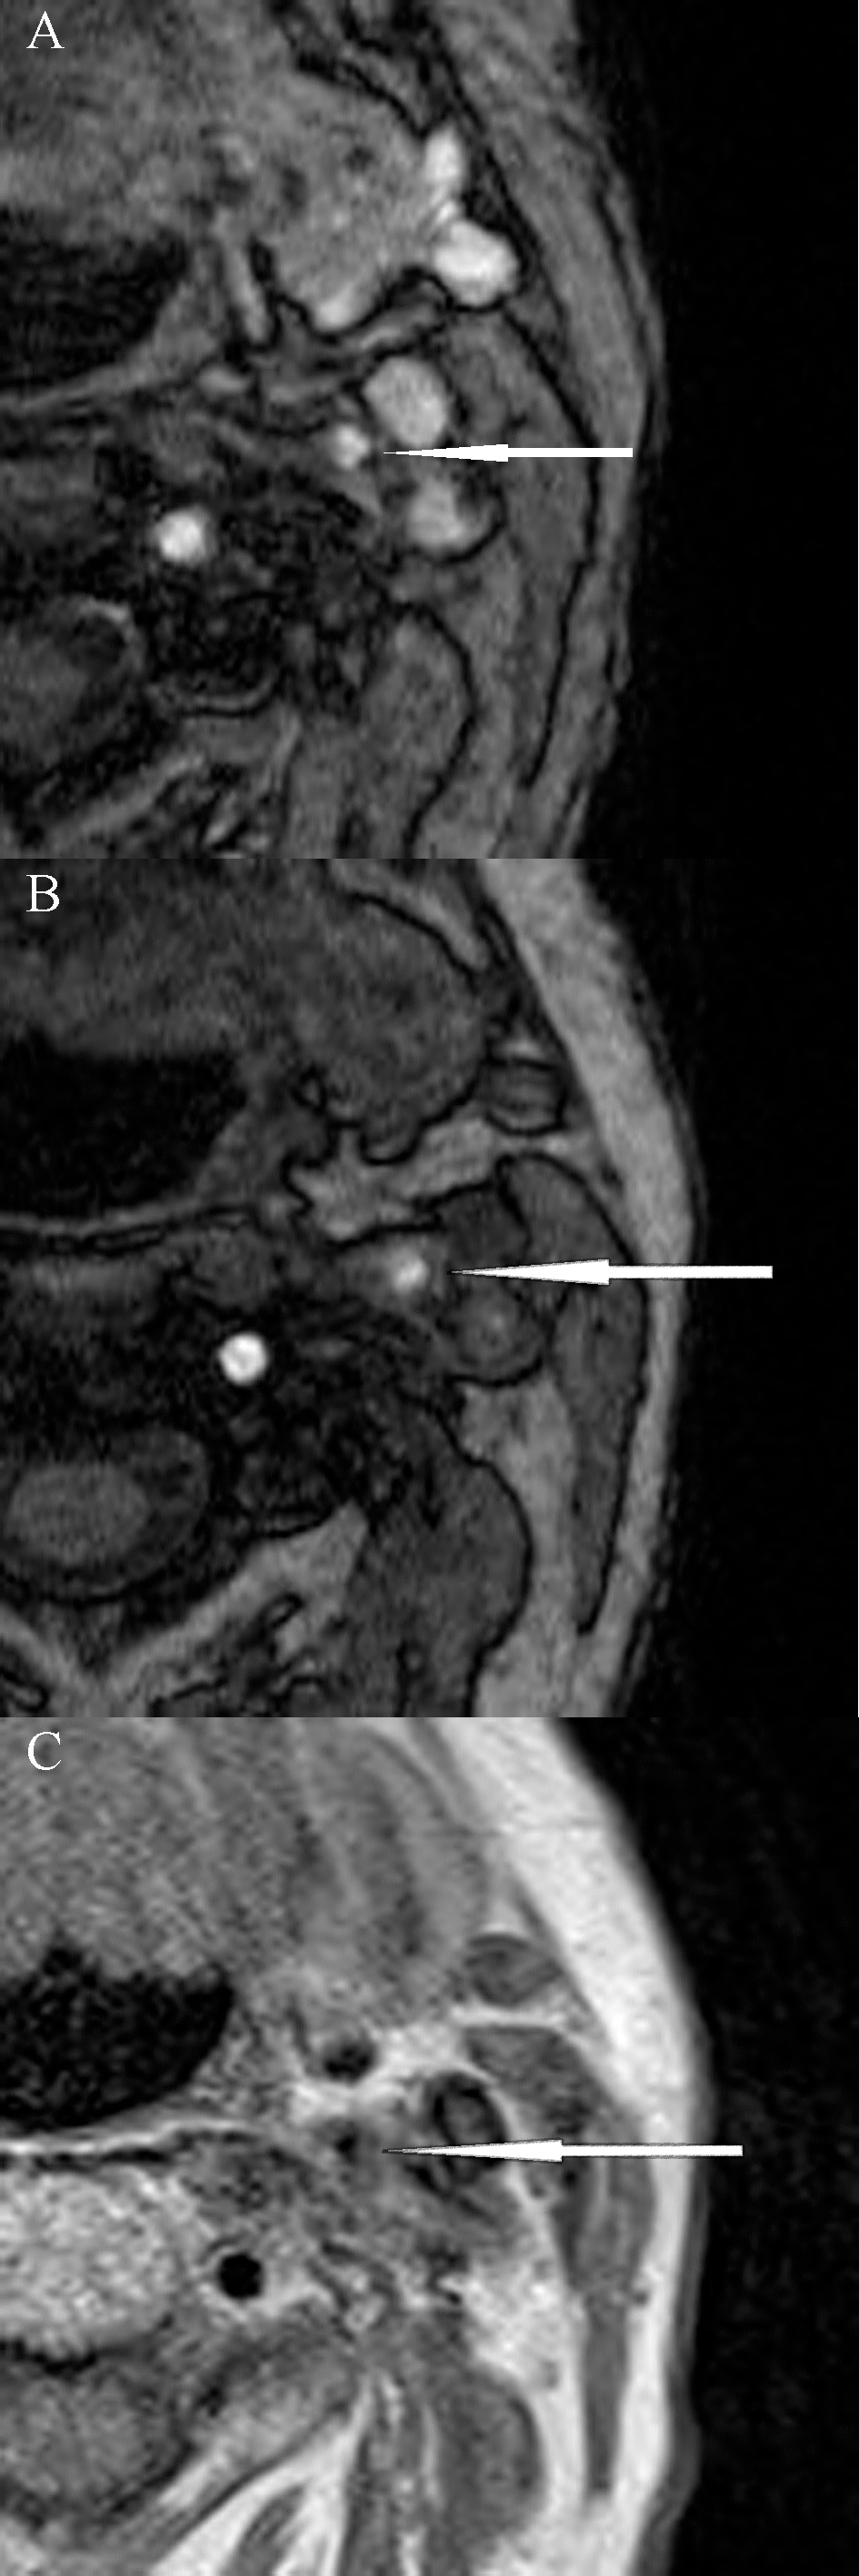

Carotid plaque features detected on preoperative MRI scan are summarized in Tables 2,3. Prevalence of unstable plaque was higher in symptomatic than asymptomatic patients, although this was not statistically significant (63% vs. 37%, p = 0.077) (Table 2, Fig. 1). The most common type of carotid plaque as per modified AHA classification was type IV–V (10 patients, 65%) (Table 3).

Fig. 1.Magnetic resonance imaging of unstable carotid plaque (modified AHA classification type VI) in a patient with symptomatic left internal carotid artery stenosis. (A) and (B) 3D-time of flight (TOF) sequences; (C) Proton density (PD) sequence.